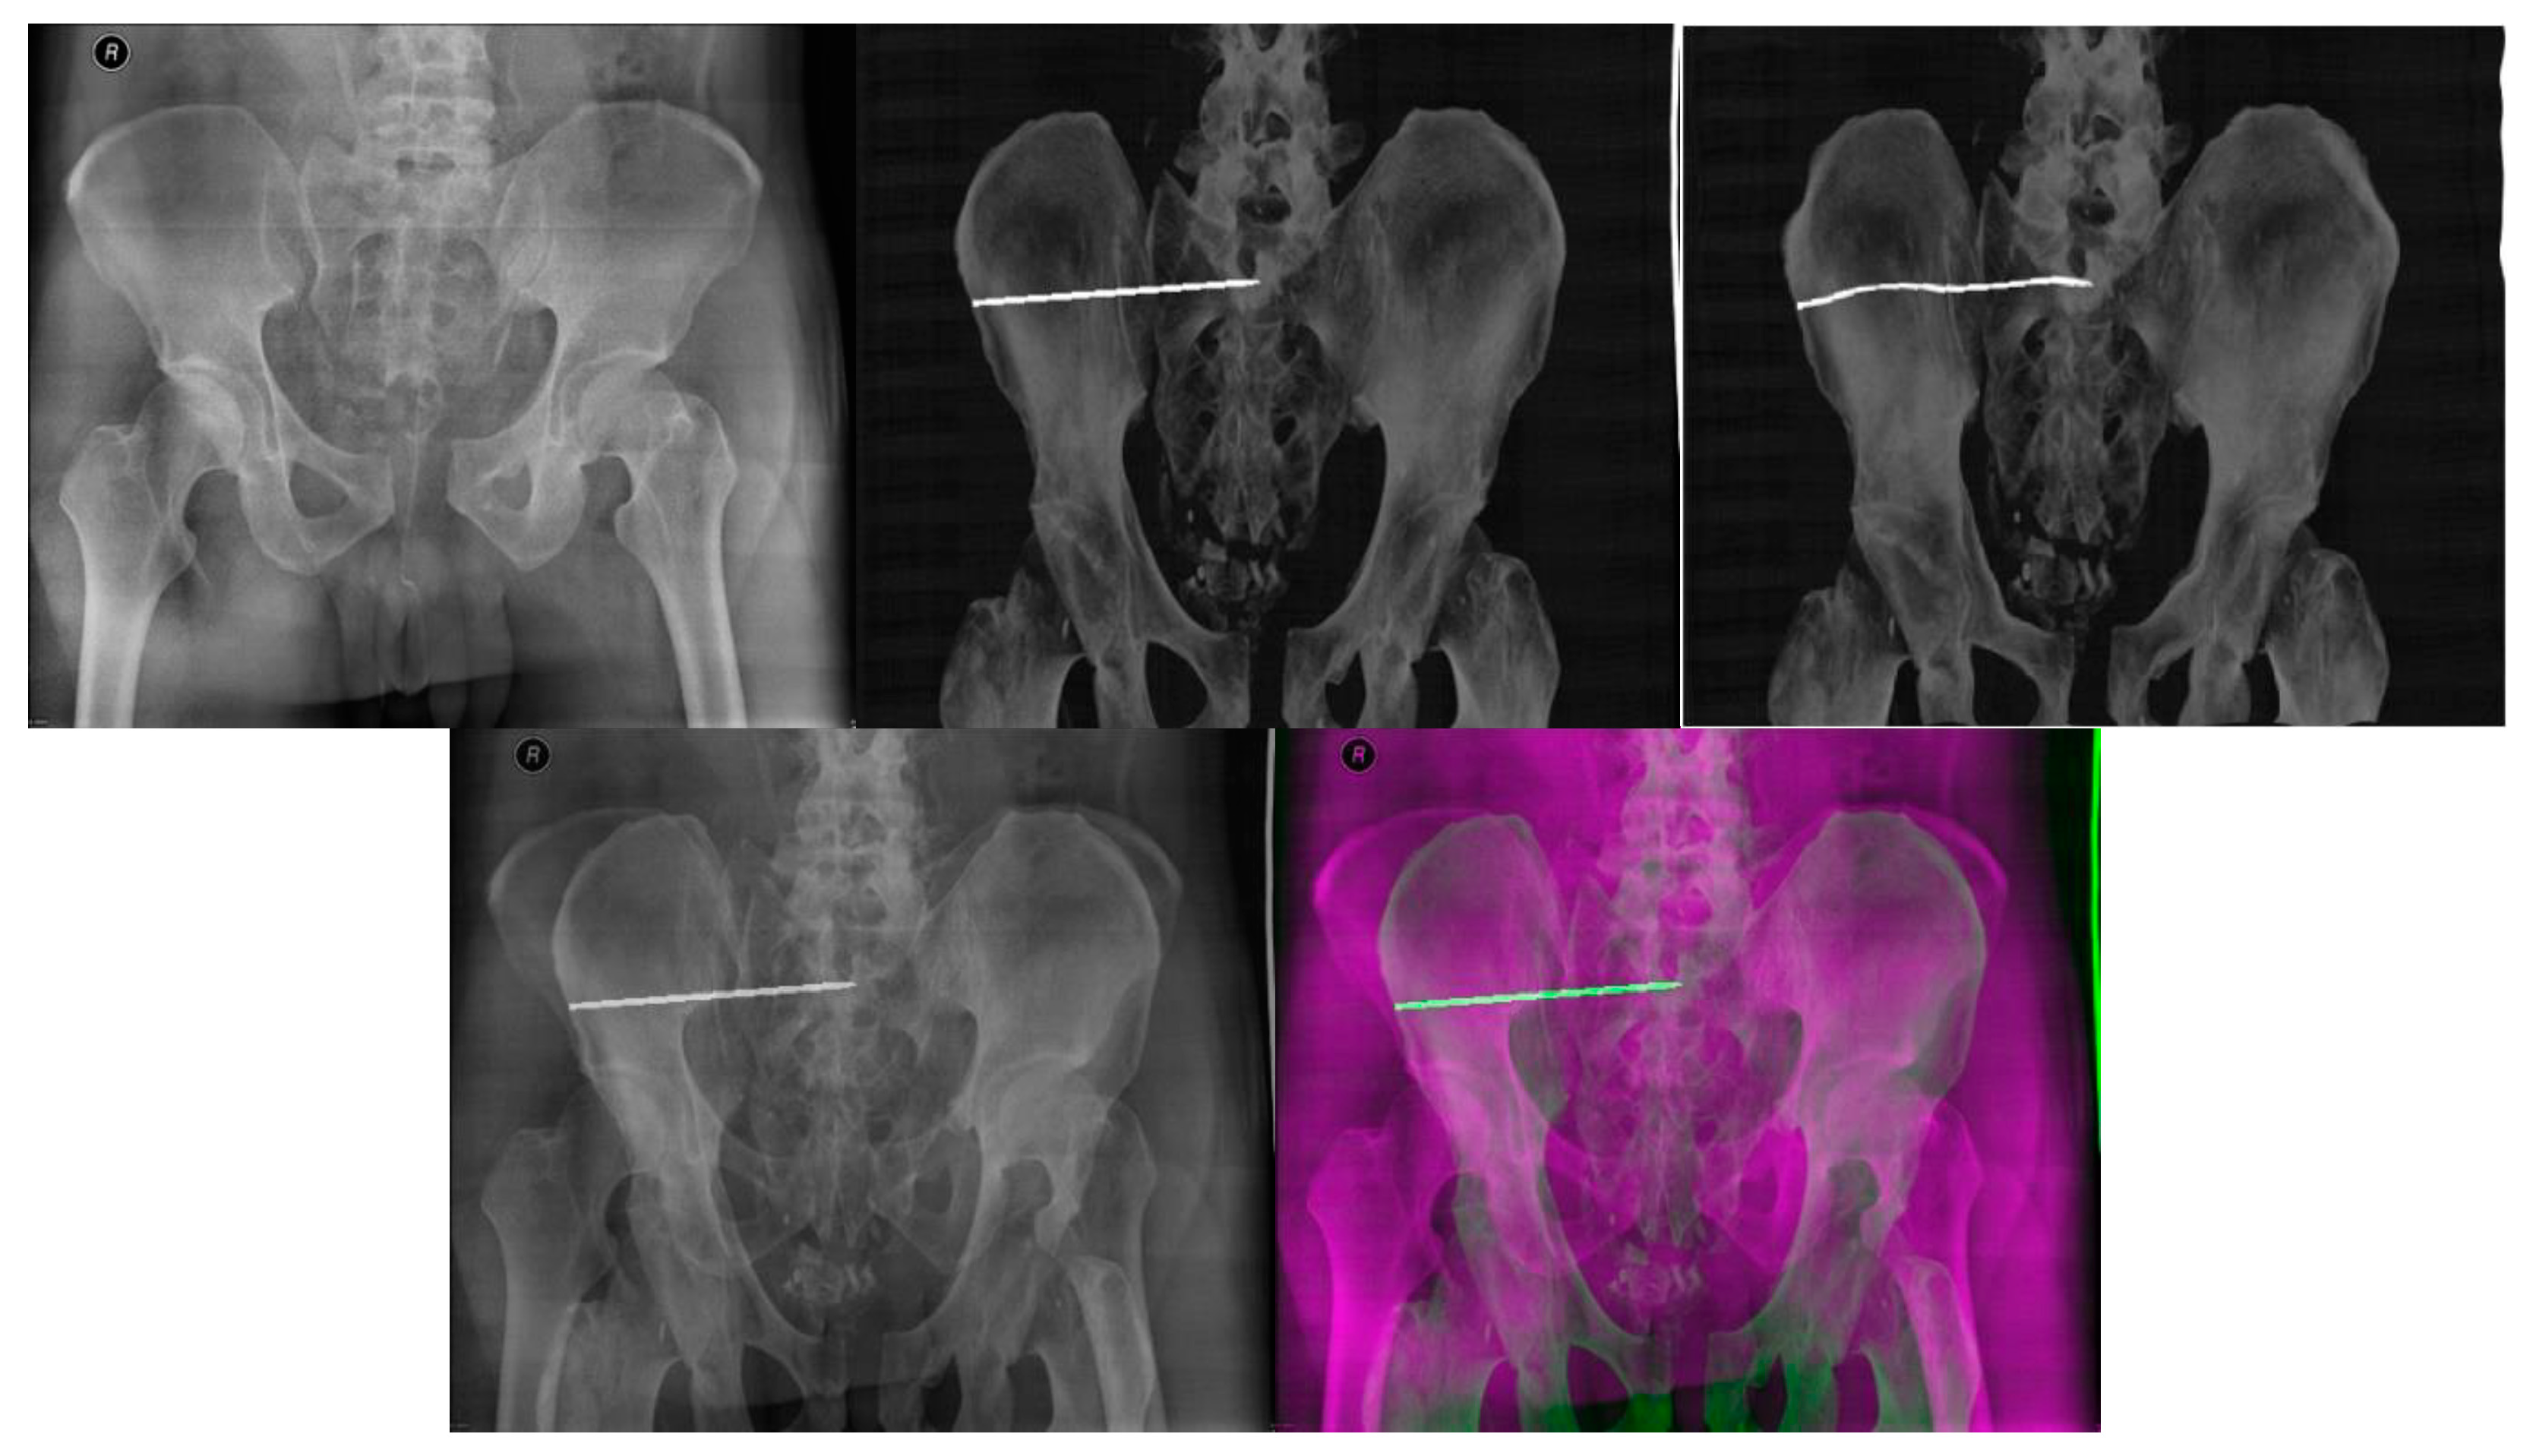

- Multimodal image registration of DRR projections to a reference X-ray image